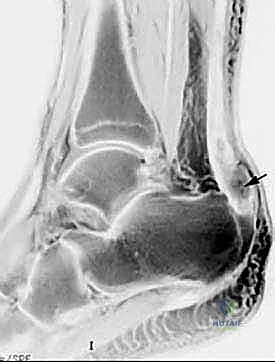

رغم أن الفحص السريري كافٍ غالباً، إلا أن التصوير الطبي يلعب دوراً مهماً في تقييم حجم التمزق والتخطيط الجراحي:

1. الموجات فوق الصوتية (Ultrasound): فحص ديناميكي ممتاز، سريع وغير مكلف، يُظهر بوضوح الفجوة بين نهايتي الوتر الممزق ويسمح بتقييم حركة نهايات الوتر أثناء تحريك القدم.

2. الرنين المغناطيسي (MRI): هو التصوير الأدق والأشمل. يوفر صوراً عالية الدقة تظهر مكان التمزق بدقة متناهية، المسافة بين نهايتي الوتر (Gap size)، جودة الأنسجة المتبقية، ووجود أي تنكس مزمن (Tendinosis) مصاحب. هذا يساعد الدكتور هطيف في تحديد ما إذا كانت تقنية "صندوق الهدايا" هي الأنسب أو إذا كانت الحالة تتطلب تطعيماً إضافياً للوتر.